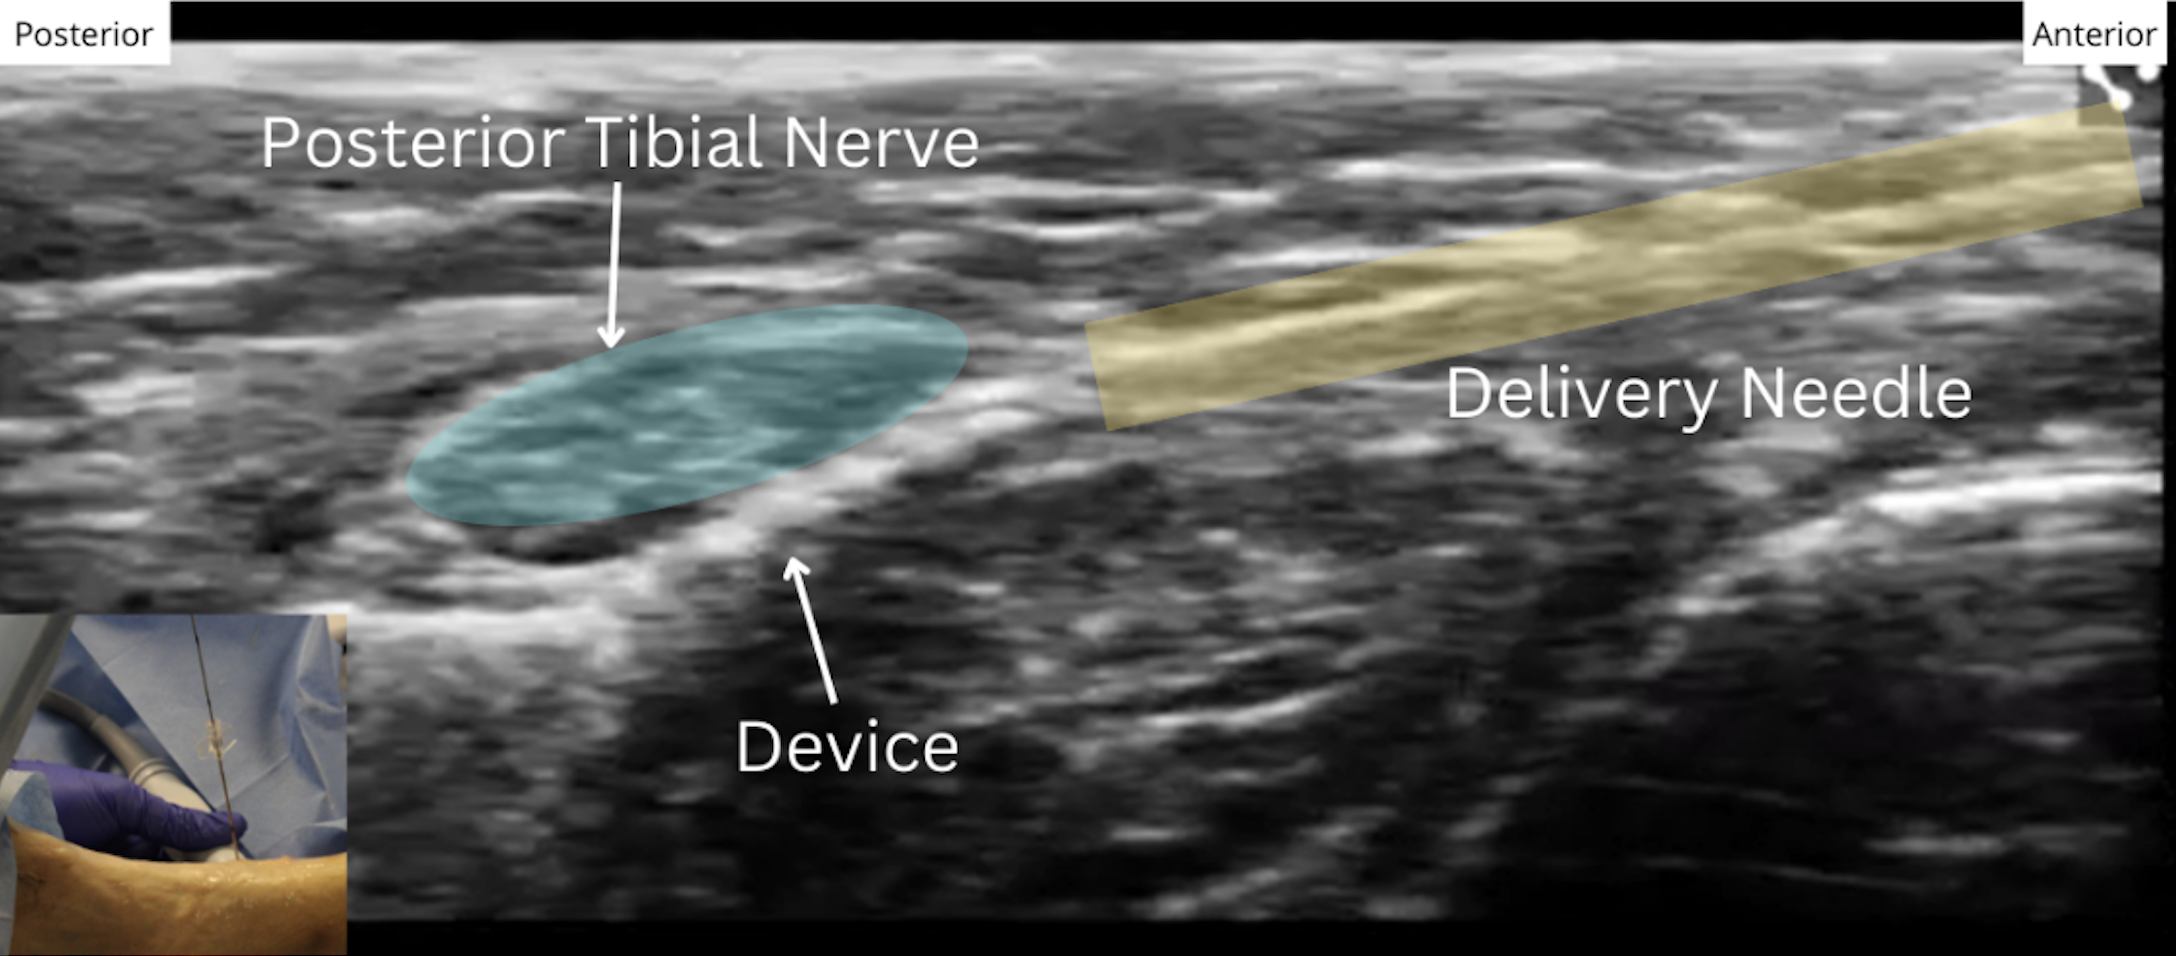

Another common neuromodulation target is the posterior tibial nerve (PTN). The Injectrode’s placement procedure allows clinicians to customize the size of each anchor (stimulating anchor, central anchor, subcutaneous collector) for each patient’s unique anatomy.

Out of plane ultrasound imaging can be used to easily identify the target nerve and allow for needle trajectory planning to minimize tissue trauma. The delivery needle is guided to the target and is angled roughly parallel to the nerve for Injectrode deployment. The Injectrode’s flexibility makes the PTN a suitable target, as the device conforms to the PTN, with the stimulating anchor capable of curving around the nerve after placement.

By creating a low-resistance path, the Injectrode is a promising approach for the future of PNS treatment.